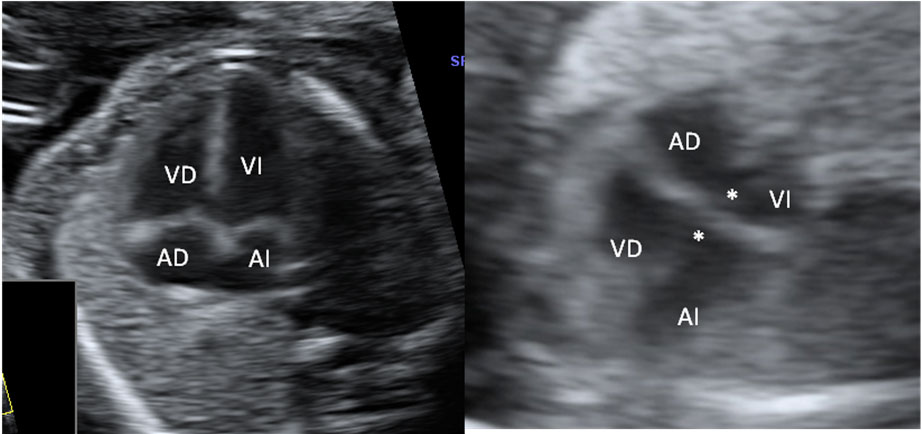

En esta imagen obtenida con una ecografía en 4D de un feto de 20 semanas de gestación se contempla cómo el bebé mueve sus brazos delante de su cara. Aún se encuentra muy delgado, ya que es a partir del tercer trimestre, sobre todo, cuando el feto empieza a acumular grasa bajo su piel.

Ecografía de bebé de 20 semanas de perfil

Podemos ver claramente los miembros superiores: el feto flexiona los brazos y los pasa por delante de la cara